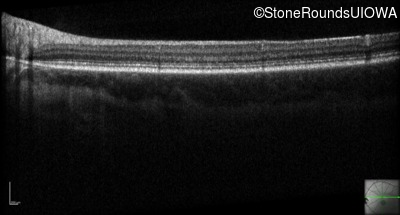

Optical Coherence Tomography - Left - 20/80

Exemplar / OCT Stack